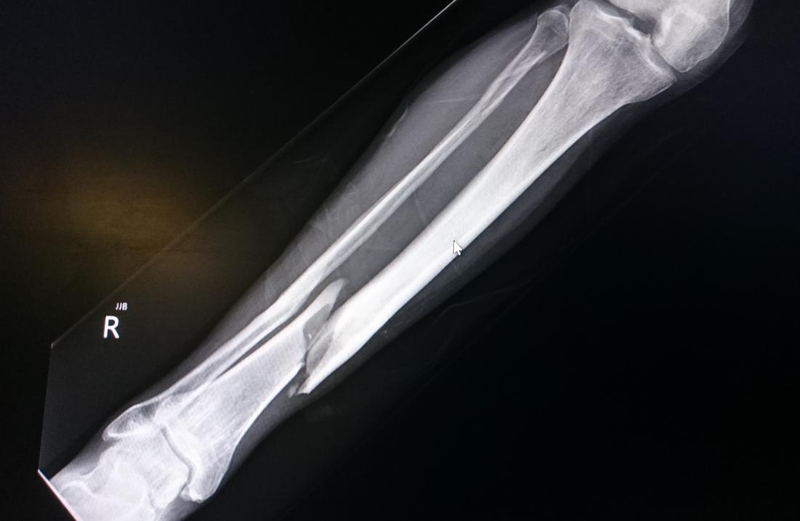

Hình ảnh gãy xương chày - Xương lớn ở chân

Sau khi khám lâm sàng với những dấu hiệu trên, bác sĩ thường chỉ định bệnh nhân thực hiện chụp X-quang để thấy rõ tình trạng xương chân hơn. Nếu phương pháp X-quang không đạt hiệu quả như mong muốn, bệnh nhân còn cần làm thêm chụp CT để thấy rõ xương bị thương, tình trạng gãy xương chày như thế nào, có mảnh vụn và tổn thương mô mềm không,... Việc chẩn đoán chính xác sẽ hỗ trợ quá trình điều trị hiệu quả hơn rất nhiều.